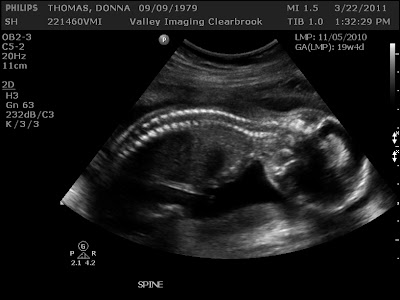

Spine: